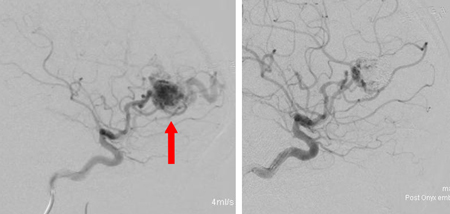

脳血管内治療は、開頭手術や放射線治療との組合せで行われるのが通常です。血管の中から異常血管の部分にマイクロカテーテルを誘導し、血管を塞栓する物質(コイル、NBCA、Onyxなど)で出血しやすい部位を処理し、あとに続く開頭手術や放射線治療をより効果的にするために有効とされています。担当される先生と、治療方針や合併症などをご相談ください。